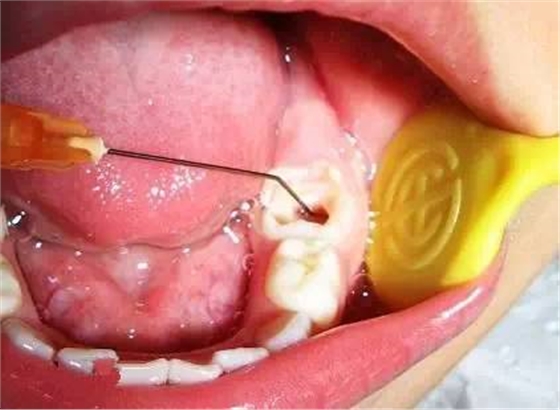

乳牙急性根尖周炎的應(yīng)急處理,首先應(yīng)建立髓腔引流,用快速鋒利的渦輪機牙鉆開髓,開放髓腔,使炎性滲出物或膿液通過根管引流。 (福建醫(yī)大口腔醫(yī)院 高生輝老師的圖片)

已形成粘膜下膿腫的還需在口腔內(nèi)的腫脹部位做局部切開排膿,而腫脹嚴重者,則需用碘仿紗條進行引流。(醫(yī)大口腔醫(yī)院 高生輝老師圖片)

2)根管預(yù)備

根管沖洗

(以上圖片引用自福建醫(yī)大附屬口腔醫(yī)院兒童科 高生輝老師的課件,非常感謝?。?

去齲,開髓,揭髓室頂。根管預(yù)備,根管沖洗。封藥。根管充填。